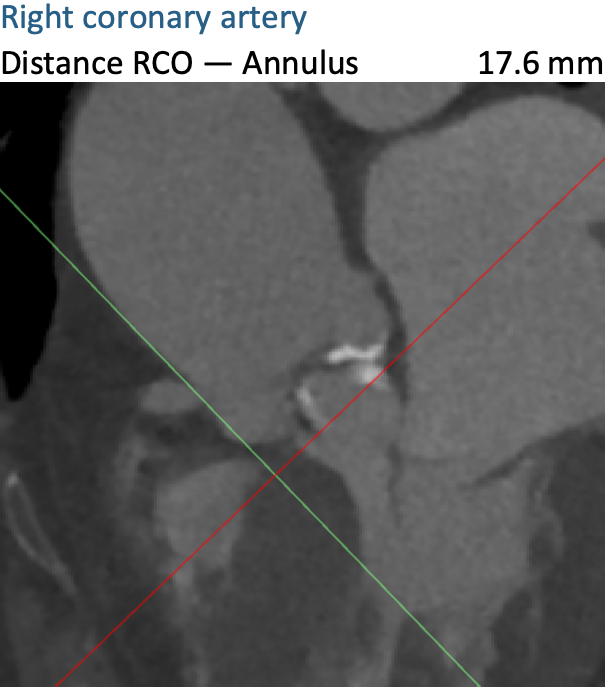

通过FEops评估冠脉风险

根据FEops报告上的左右冠脉CT截面得知RCA Height:17.6mm、LCA Height:11.7mm,左冠脉高度小于12mm是存在一定阻塞风险的,但是通过植入前后的3D模型对比瓣叶形态得知冠脉风险比较低。